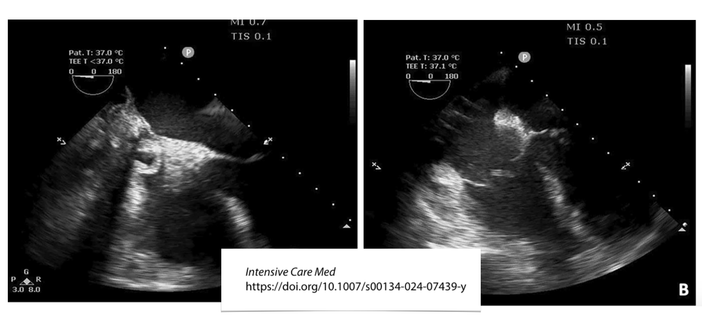

What is happening in this 44-year-old man on VA #ECMO??

๐Ÿšจ #ECPR after 30 min of refractory cardiac arrest post-myocardial infarction

๐Ÿซ€ recovered native cardiac activity but severe postresuscitation vasoplegia leading to important fluid filling to maintain #extracorporeal blood flow

๐Ÿ–ฅ๏ธ TEE showed right atrial collapse

โ€ฆ. cardiac tamponade?? Collapse reversed within seconds during a transient reduction in EBF

Right atrial collapse mimicking cardiac tamponade in a patient on veno-arterial extracorporeal membrane oxygenation